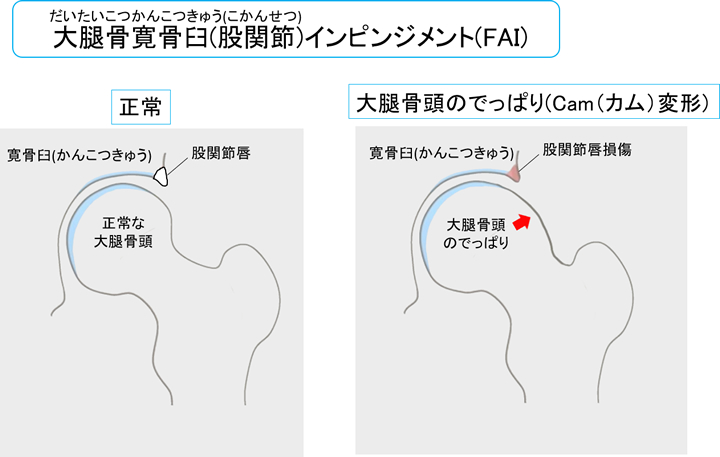

唇裂傷は誰でも発症する可能性がありますが、より経験しやすい人もいます。最も一般的な根本的な原因は、腰骨の衝突です。

股関節インピンジメントとは、大腿骨の頭が寛骨の受け皿を挟むことです。それは、大腿骨と骨盤の間に反復的な非定型接触を引き起こします。